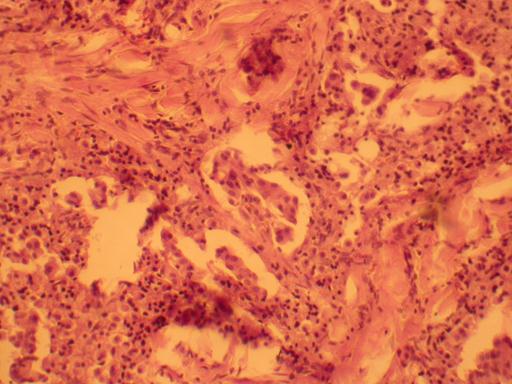

Рисунок 90 - Фолликулярный рак щитовидной железы.

Рисунок 91 - Папиллярный рак щитовидной железы.